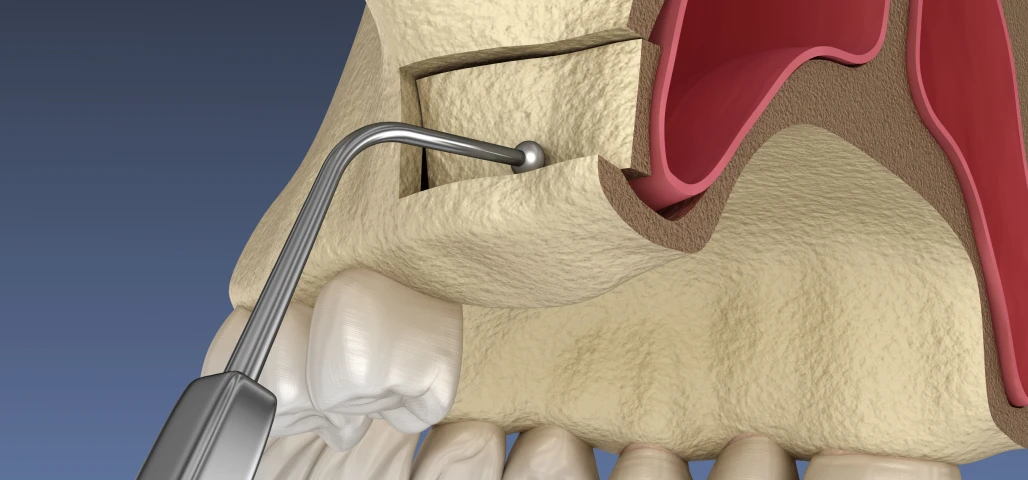

La chirurgie orale regroupe un ensemble d’interventions réalisées au niveau de la bouche, des dents et des mâchoires, allant de l’extraction des dents de sagesse aux actes plus complexes comme les kystes, les freinectomies ou les préparations implantaires.